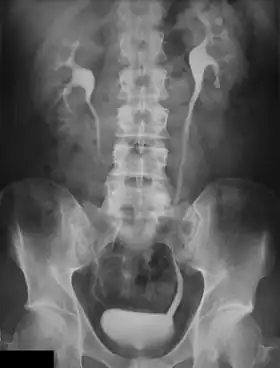

An intravenous pyelogram (IVP), also called an intravenous urogram (IVU), is a radiological procedure used to visualize abnormalities of the urinary system, including the kidneys, ureters, and bladder. Unlike a kidneys, ureters, and bladder x-ray (KUB), which is a plain (that is, noncontrast) radiograph, an IVP uses contrast to highlight the urinary tract.

An injection of X-ray contrast medium is given to a patient via a needle or cannula into the vein,[7] typically in the antecubital fossa of arm. The contrast is excreted or removed from the bloodstream via the kidneys, and the contrast media becomes visible on X-rays almost immediately after injection. X-rays are taken at specific time intervals to capture the contrast as it travels through the different parts of the urinary system.[7] At the end of the test, a person is asked to pass urine and a final X-ray is taken.[7]

Immediately after the contrast is administered, it appears on an X-ray as a 'renal blush'. This is the contrast being filtered through the cortex. At an interval of 3 minutes, the renal blush is still evident (to a lesser extent) but the calyces and renal pelvis are now visible. At 9 to 13 minutes the contrast begins to empty into the ureters and travel to the bladder which has now begun to fill. To visualize the bladder correctly, a post micturition X-ray is taken, so that the bulk of the contrast (which can mask a pathology) is emptied.